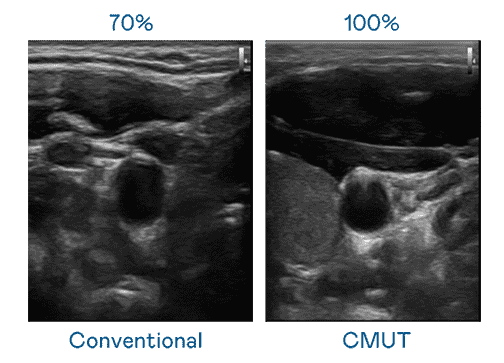

CMUT 技术是一种用电容式微机电元件来产生超音波讯号的技术。。与传统 PZT 压电式技术相比,,CMUT 频宽增加 30%,,,,更宽频的超音波讯号让影像解析度大幅提升,,是实现高影像品质医疗超音波扫描、、、、促进精准医疗发展的关键技术。。

超音波影像的解析度高低,,首先取决于探头能发出的讯号频宽。。z6尊龙 CMUT 可提供高清晰的超音波讯号,,,提供高频宽、、、高灵敏度、、、影像纹理细节更高的超音波影像,,,协助医护人员缩短影像判读时间及利用精准的医疗影像进行诊断。。。。